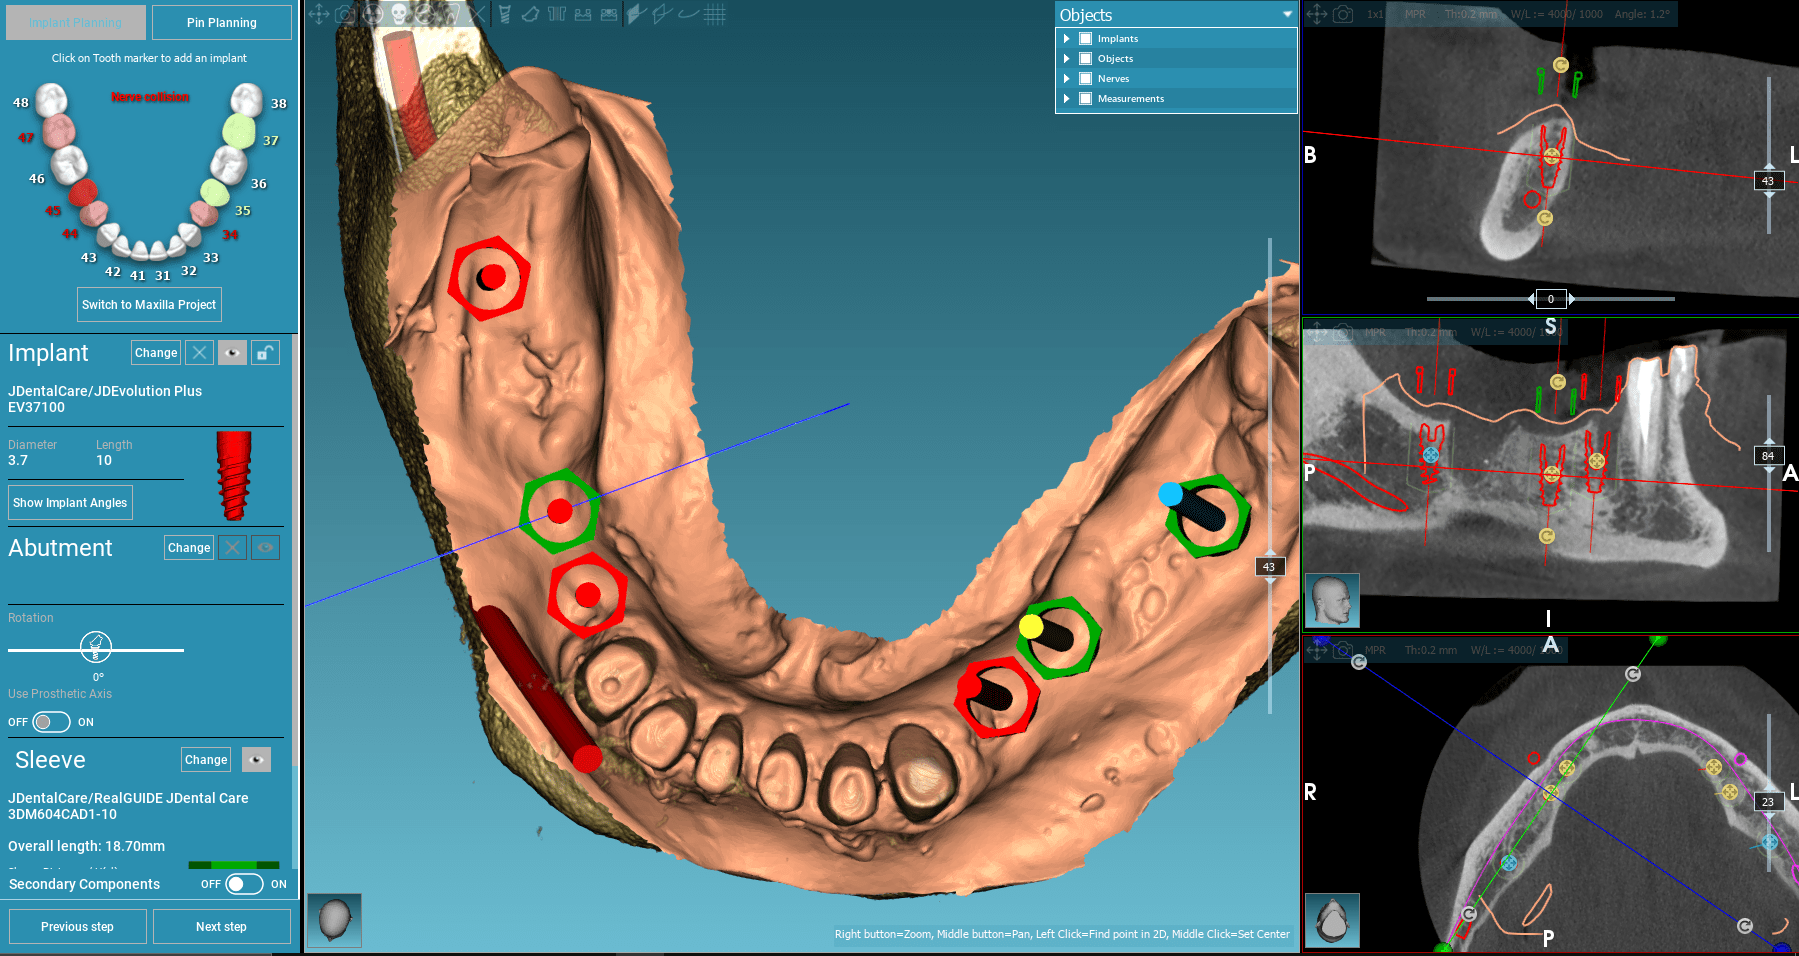

Het aflezen van de beelden opgenomen met de 3D scan worden met speciale software door de chirurg uitgelezen en beoordeeld. In onze kliniek gebeurt dit regelmatig en is dit een standaard praktijk voor ons. Besluiten wat we kunnen doen is een enorme verantwoordelijkheid en deze moet serieus genomen worden omdat elke patiën uniek is. Puntje bij paaltje is dit het belangijkste onderzoek wat gedaan moet worden en u hebt het recht om er alles over te weten.